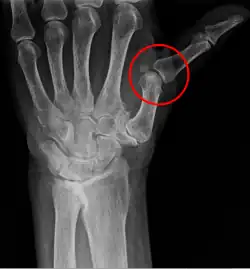

Podwichnięcie (łac. subluxatio) – niezupełne zwichnięcie polegające tylko na przesunięciu powierzchni stawowych względem siebie, bez całkowitej utraty kontaktu ze sobą.

U dzieci do trzeciego roku życia może wystąpić podwichnięcie główki kości promieniowej na skutek silnego pociągnięcia za rękę[2].